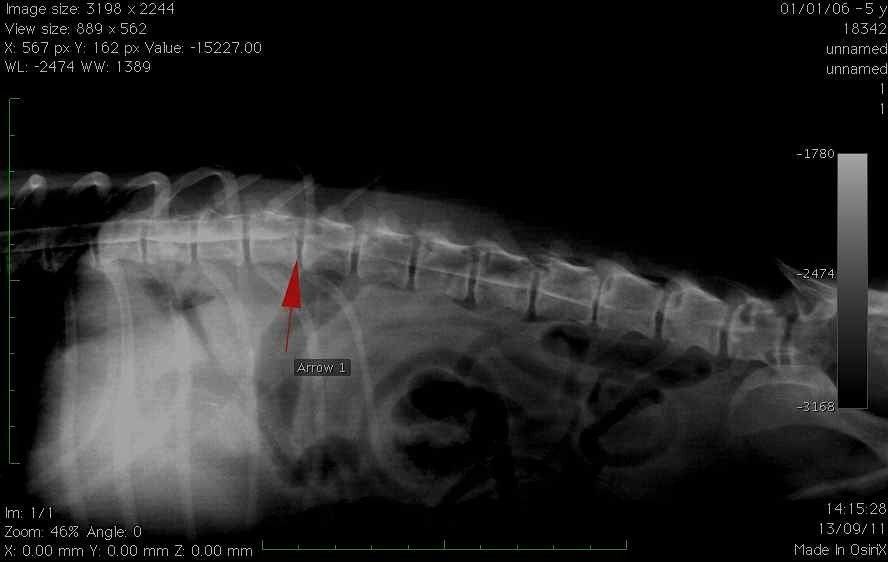

- Die Operationen von Bandscheibenvorfall die die ersten Pathologien geworden sind, denen man begegnet ist Neurologie im Hund.